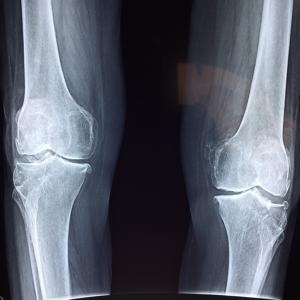

뇌졸증 검사의 다른 방법으로는 영상 검사가 있습니다. 뇌의 CT 스캔, MRI, 혈관조영술 등의 영상 검사를 통해 뇌의 형태와 혈관 상태를 확인할 수 있습니다. 이러한 영상 검사는 뇌졸증의 원인을 파악하고 혈류 장애를 확인하는 데 도움이 됩니다.